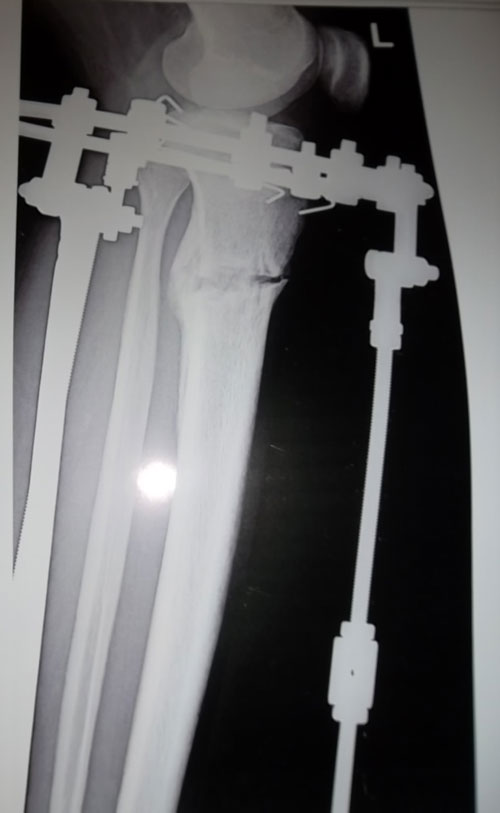

- Диагноз: О- образная деформация нижних конечностей

- Дата операции.: 30.01.2013

- Дата снятия аппаратов.: 04.05.2013

- Срок лечения.: 92 дня

На фиксации.Первый раз (на 23-ий день после операции) пошла без дополнительных средств опоры.

Первые самостоятельные шажки без дополнительных средств опоры на 23-ий день после операции.

Всем привет!Я с Алматы,мне 22.Приехала в Павлодар 24го сентября.25го утром сдала анализы,27го оперировали.После операций я не почувствовала боли и на следующий день я самостоятельно стала ходить с ходунком.Когда начила ходить были боли но терпимо.После операций на седьмой день вернее 4го ноября наш врач Н.Н начел крутить.Уже в тот день я увидела результат круток.Я в день ходила по 3,4часа.В общей сложности мне крутили ноги 15дней.А на последний день я увидела коласальный результат.На 23 день после операций начала ходить без ходунка.Спасибо нашему доктору.Руки у него золотые.Наконец-то мои мечты сбылись.И спасибо девченкам которые меня поддерживали.